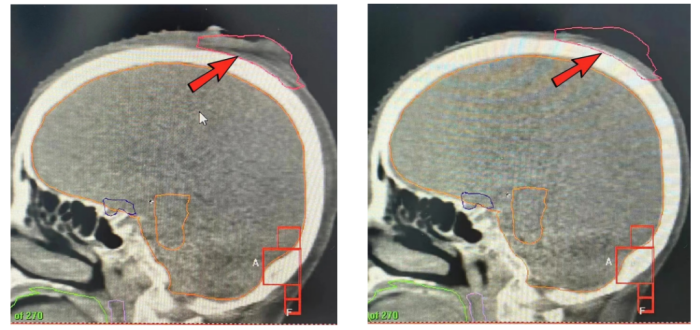

因患者高龄,家属担心老人手术风险,考虑再三后选择了肿瘤科的放射治疗。而头部解剖结构复杂,放疗需要精确定位、精准计划和精准照射,以保证在肿瘤得到有效治疗的同时,还能减少对周围正常组织的损伤。经肿瘤科医师团队讨论后为宋奶奶制定了个性化的放射治疗方案。

治疗前头皮可见突出肿块 放疗后头皮肿块明显缩小